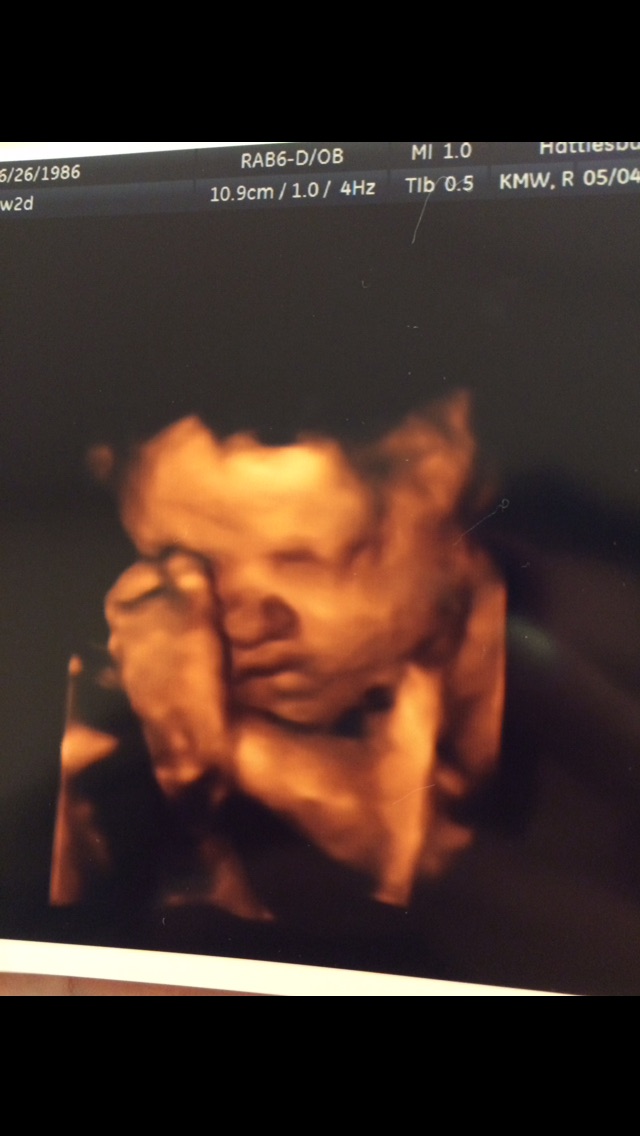

The second picture is my first born when he was 4 months and the bottom is the new addition :)